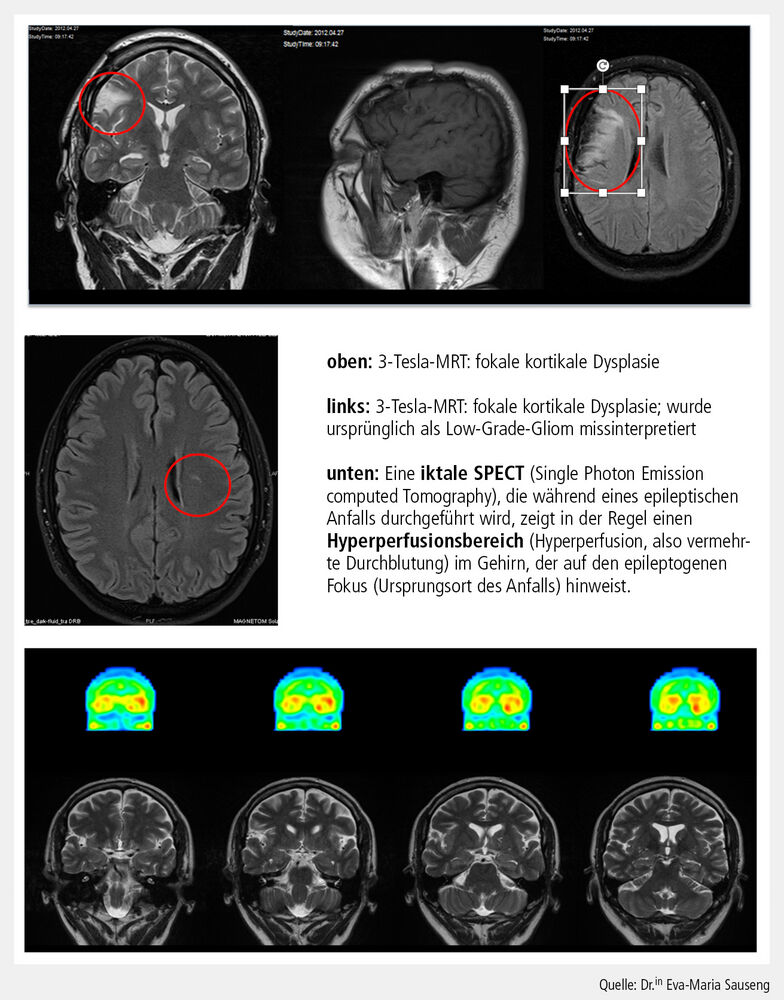

PET und SPECT

Neben der strukturellen Bildgebung gewinnen funktionelle Verfahren an Bedeutung. Die Positronenemissionstomografie (PET), vor allem mit 18F-FDG, erlaubt die Darstellung interiktaler Hypometabolismen, die mit epileptogenen Zonen korrelieren. In Kombination mit MRT (PET/MRT) lassen sich metabolische und strukturelle Informationen in einem einzigen Untersuchungsgang erfassen, was die diagnostische Sensitivität erhöht. Ein weiterer innovativer Ansatz ist die iktale Single Photon Emission Computed Tomography (SPECT) mit Subtraktion und MRT-Koregistrierung (SISCOM). Diese Methode ermöglicht die präzise Lokalisation der Anfallsursprungszone durch Darstellung von Perfusionsänderungen während eines Anfalls (Abb. 2). Studien zeigen, dass SISCOM die chirurgische Planung besonders bei komplexen und multilokulären Epilepsien unterstützt.

Abb. 2: Multimodale Bildgebung (MRT, SPECT)